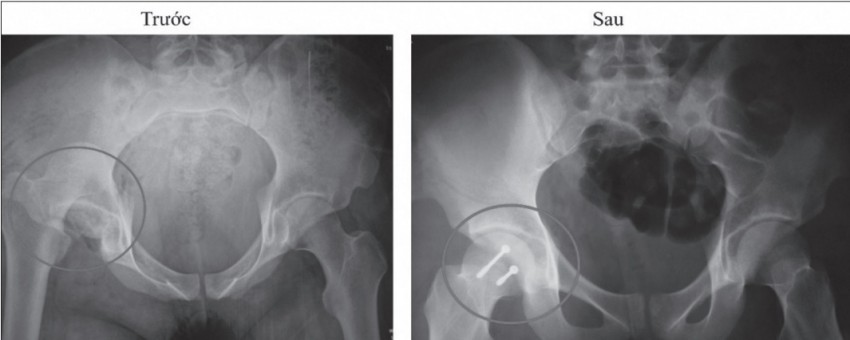

Ảnh chụp chỏm xương trước và sau khi phẫu thuật.